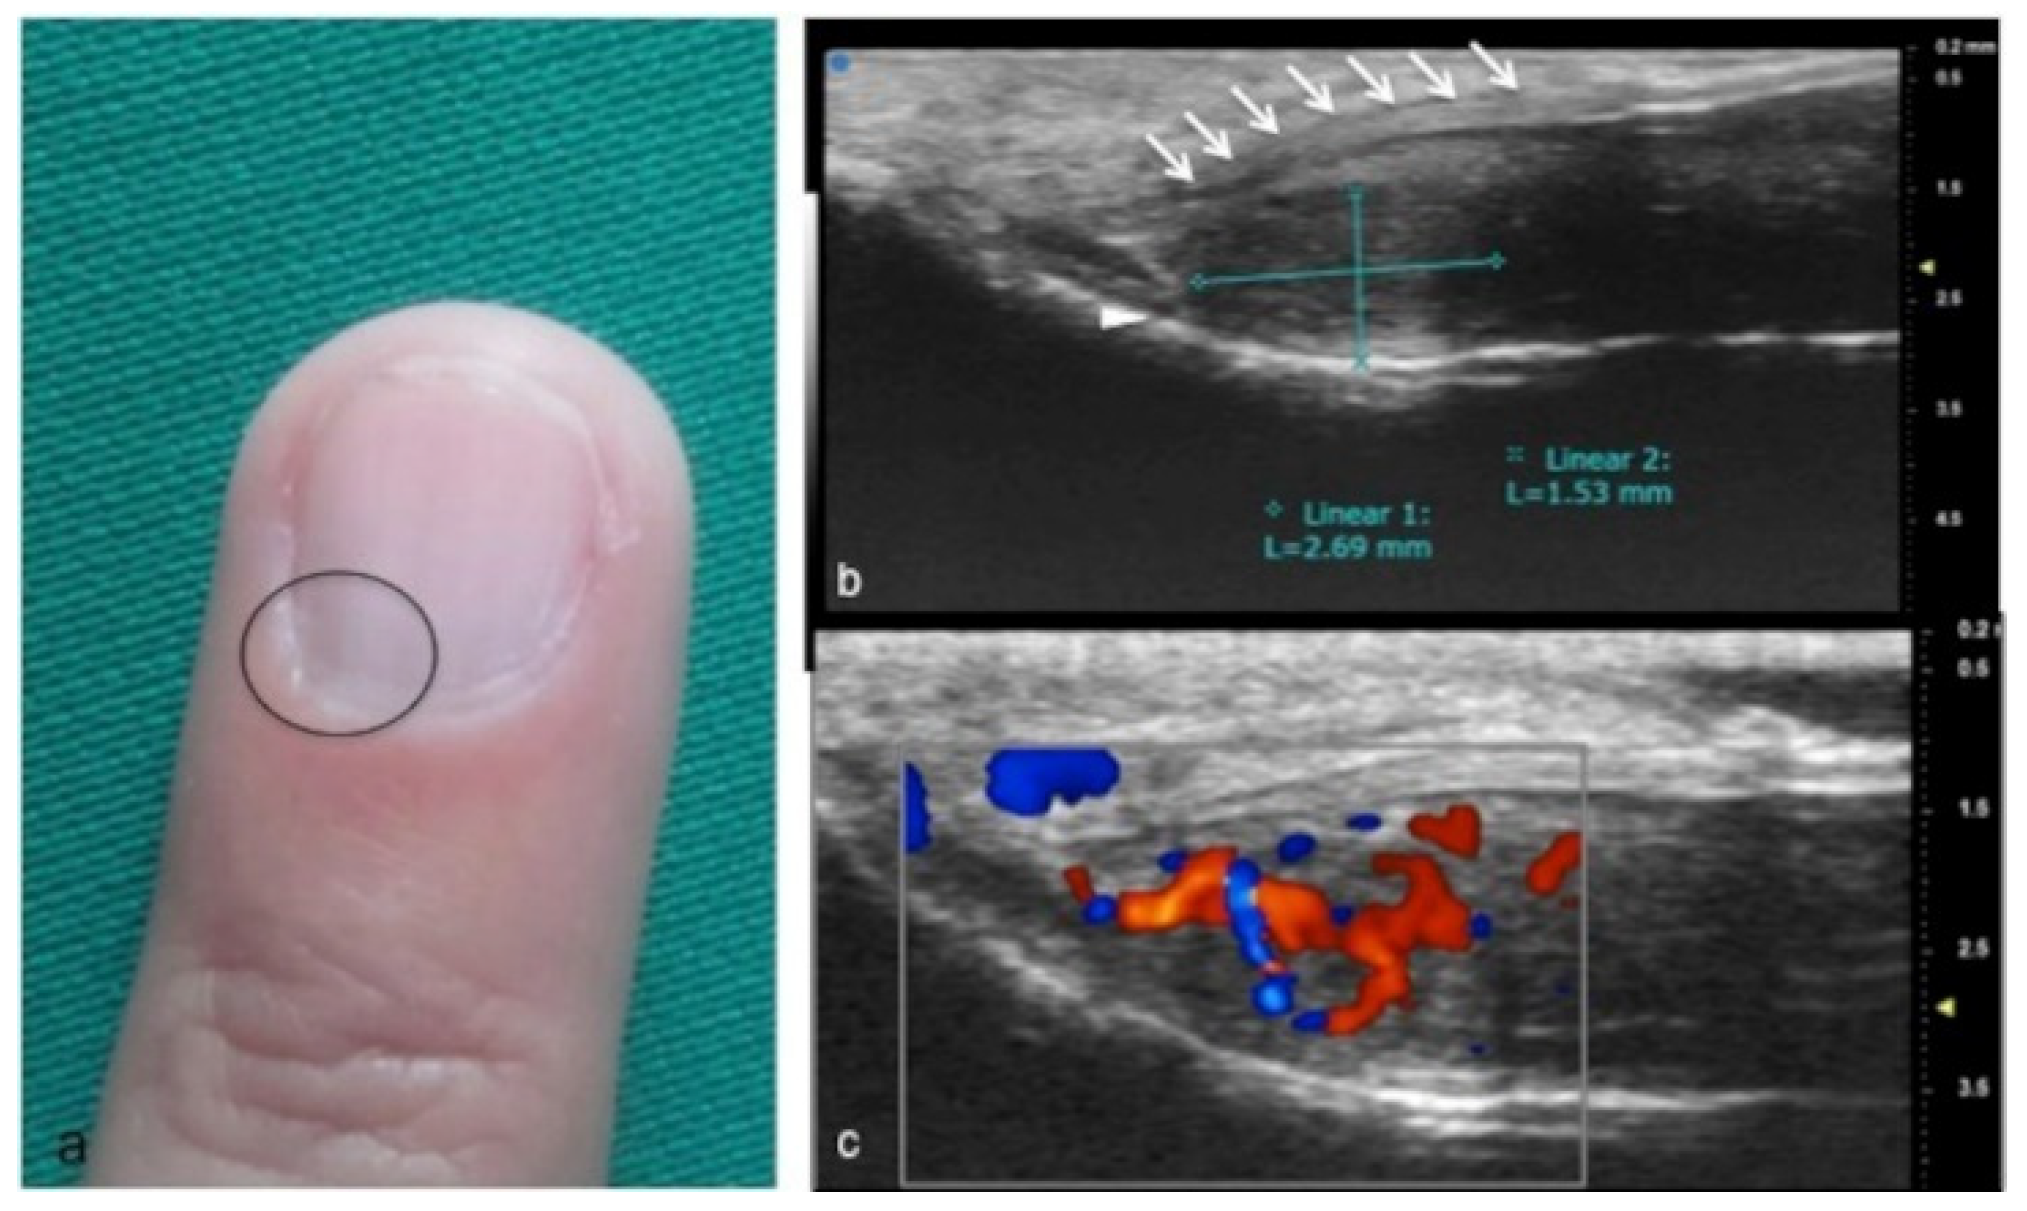

Figure 12.

Glomus tumor in the subungual space. No clear alterations were visible during clinical examination at the site of pain (circle in (a)). In (b), UHFUS effectively demonstrates the presence of a hypo-isoechogenic nodule (calibers) in contact with the adjacent phalangeal bone (arrowhead) under the nail plate (arrows). Note the small deformation of the nail plate. Mild vascularization on color Doppler was present (c).

Glomus tumors are rare, benign, vascular neoplasms arising from the glomus body, which is a contractile neuromyoarterial structure found in the reticular dermis. This structure controls blood pressure and temperature by regulating blood flow in the cutaneous vasculature. Hyperplasia in any of these parts can lead to tumor formation, which is extremely painful. Glomus tumors account for 1–5% of soft-tissue tumors of the hand, and 75% of them are subungual in location. Other less commonly involved sites in the hand are the nail matrix, nail bed, and pulp of the finger. The delay in diagnosing these tumors for many years is a significant problem. It is not uncommon that patients are easily misdiagnosed with conditions such as neuropathic complaints, arthritis, or neuralgia and undergo unsuitable treatment. For these reasons, when the clinical examination is equivocal, noninvasive imaging techniques may be needed to aid in the diagnosis and delineate the anatomy preoperatively. Complete surgical excision of the tumor is the only effective treatment. Incomplete excision is considered the main cause of recurrence. US follow-up and/or intraoperative US may be useful for reducing recurrence and ensuring adequate resection, and the UHFUS tool is promising in this field [56].